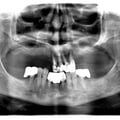

Імплантація 16,17,18 без врахування жодних правил оклюзії та знань в імплантології